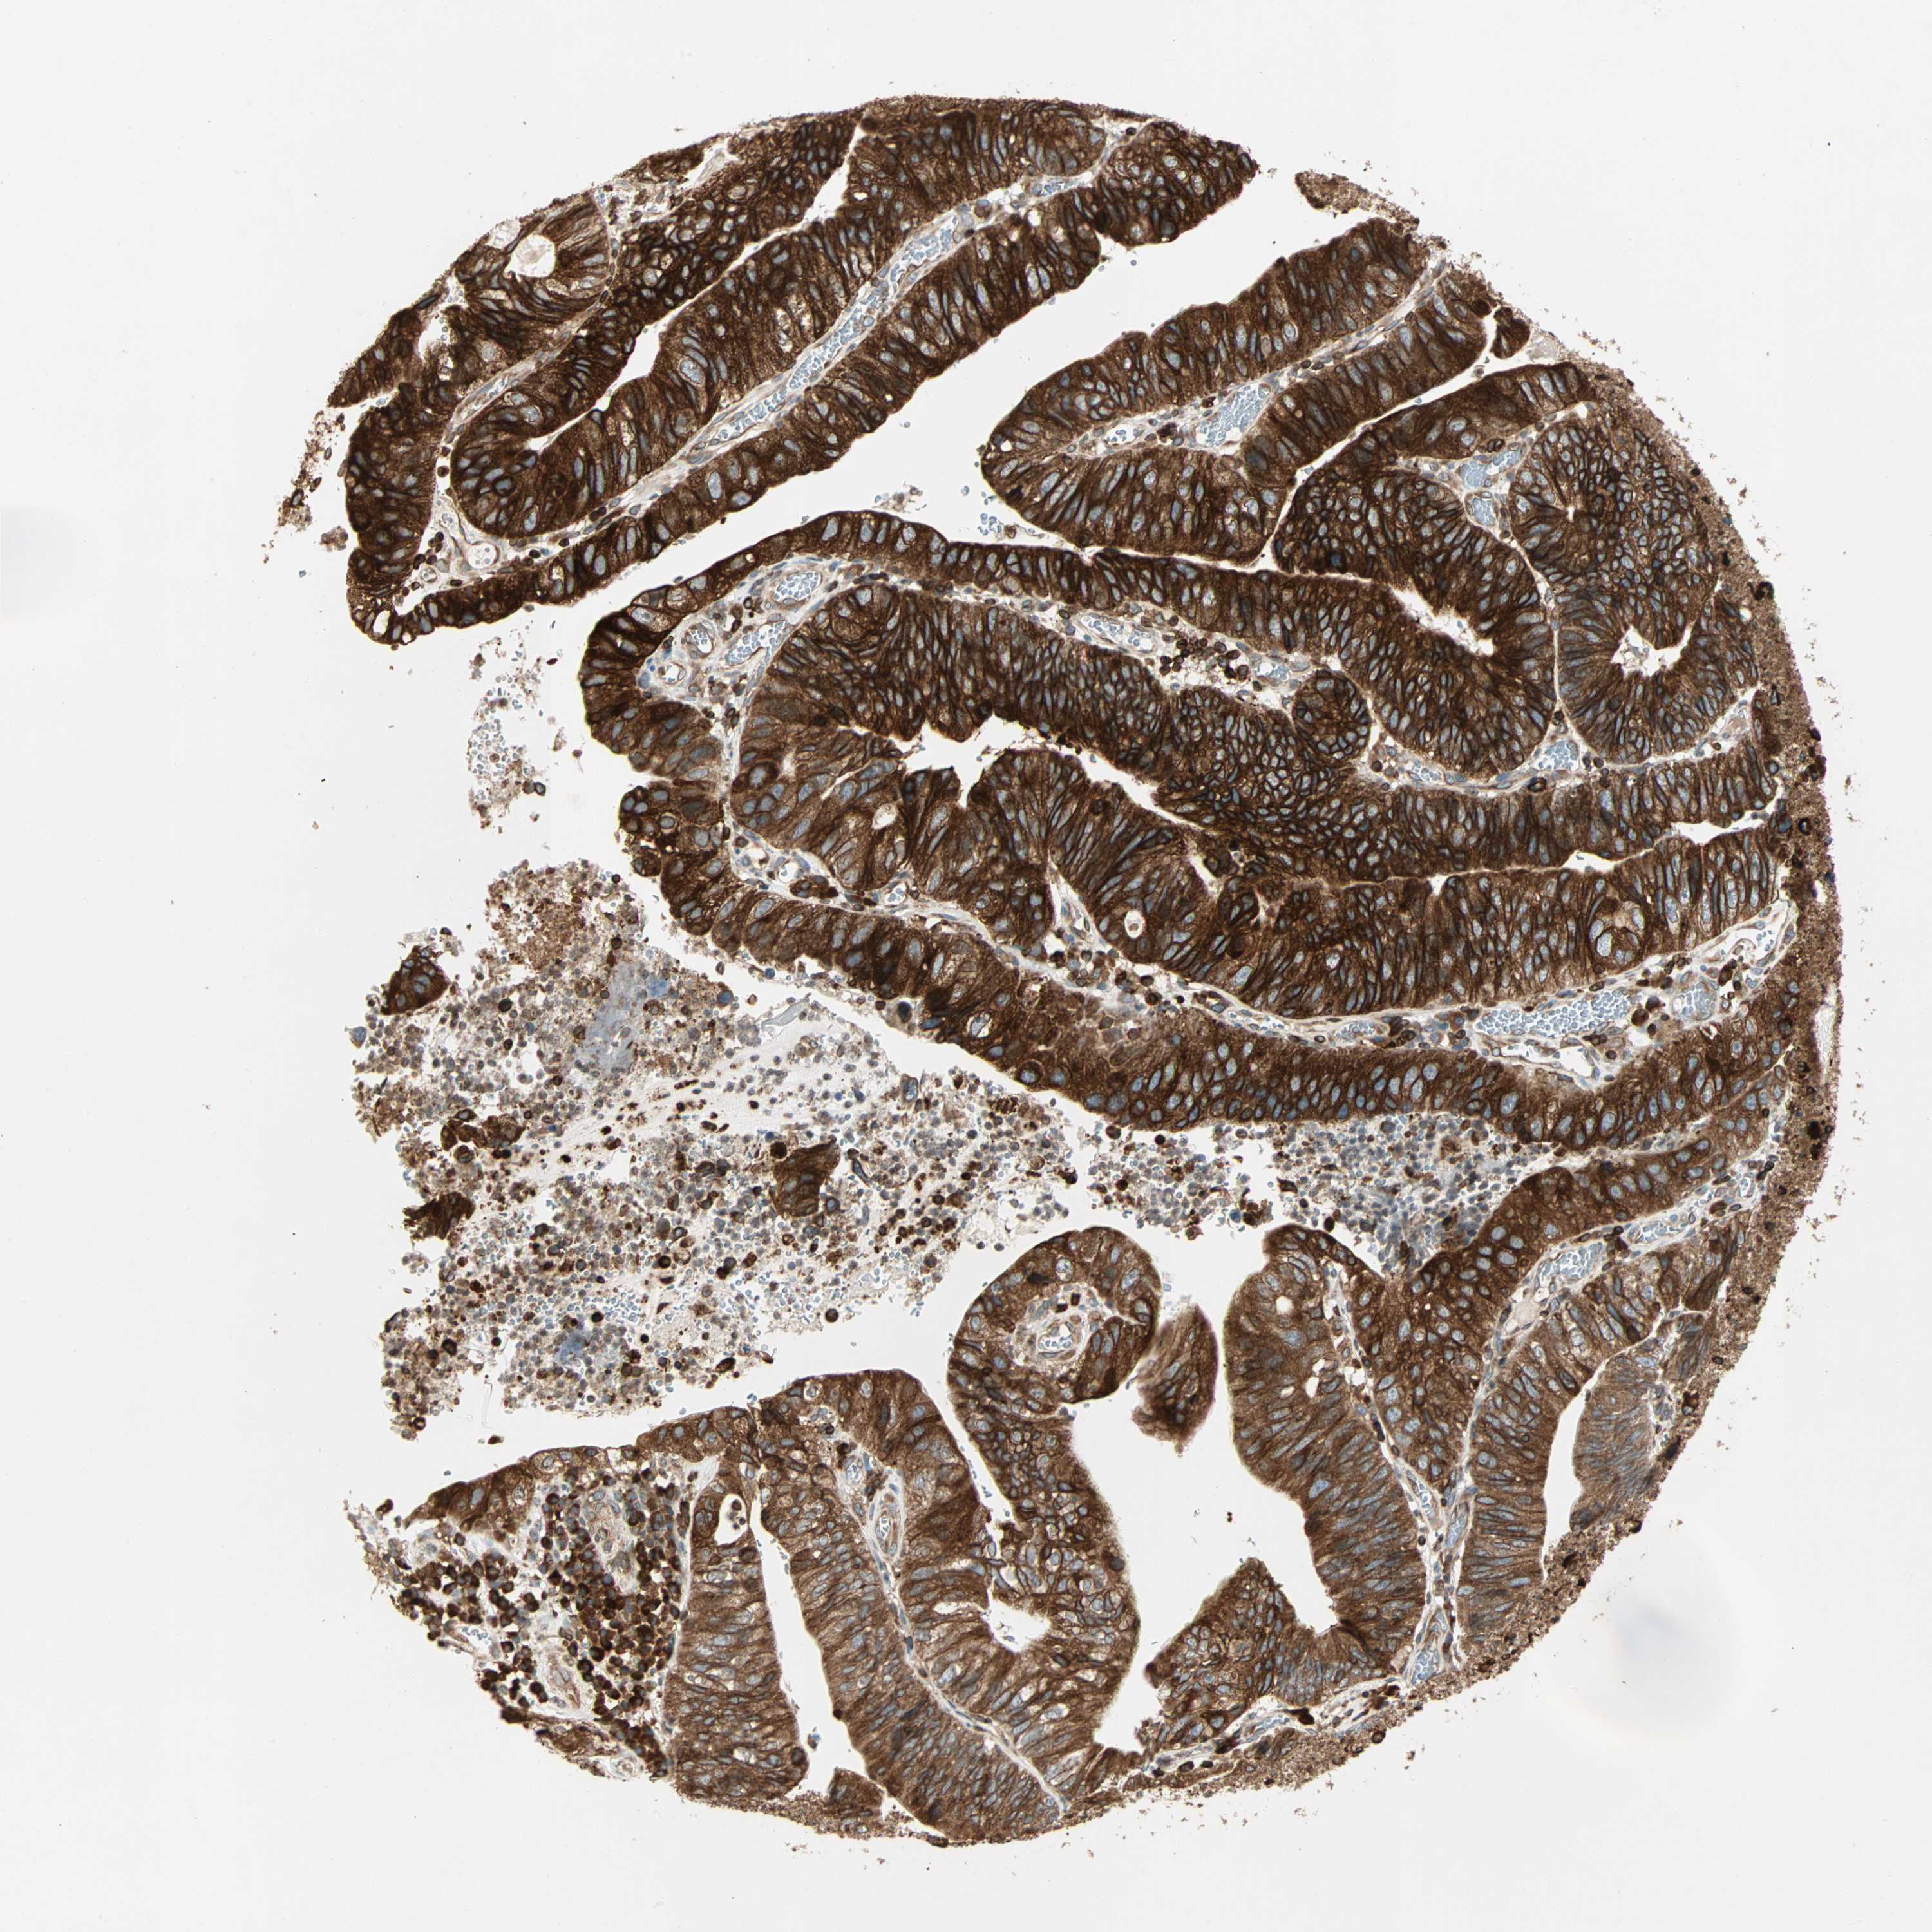

STOMACH CANCER - Protein expressioni

A mouse-over function shows sample information and annotation data. Click on an image to view it in a full screen mode. Samples can be filtered based on level of antibody staining by selecting one or several of the following categories: high, medium, low and not detected. The assay and annotation is described here.

Note that samples used for immunohistochemistry by the Human Protein Atlas do not correspond to samples in the TCGA dataset.

Antibody stainingi

Antibody staining in the annotated cell types in the current human tissue is reported as not detected, low, medium, or high, based on conventional immunohistochemistry profiling in selected tissues. This score is based on the combination of the staining intensity and fraction of stained cells.

Each image is clickable and will lead to virtual microscopy that enables deeper exploration of all samples and also displays staining intensity scores, fraction scores and subcellular localization as well as patient and tissue information for each sample.

Antibody HPA007066

Staining

High

Medium

Low

Not detected

Intensity

Strong

Moderate

Weak

Negative

Quantity

>75%

75%-25%

<25%

None

Location

Nuclear

Cytoplasmic/membranous

Cytoplasmic/membranous,nuclear

Adenocarcinoma, NOS